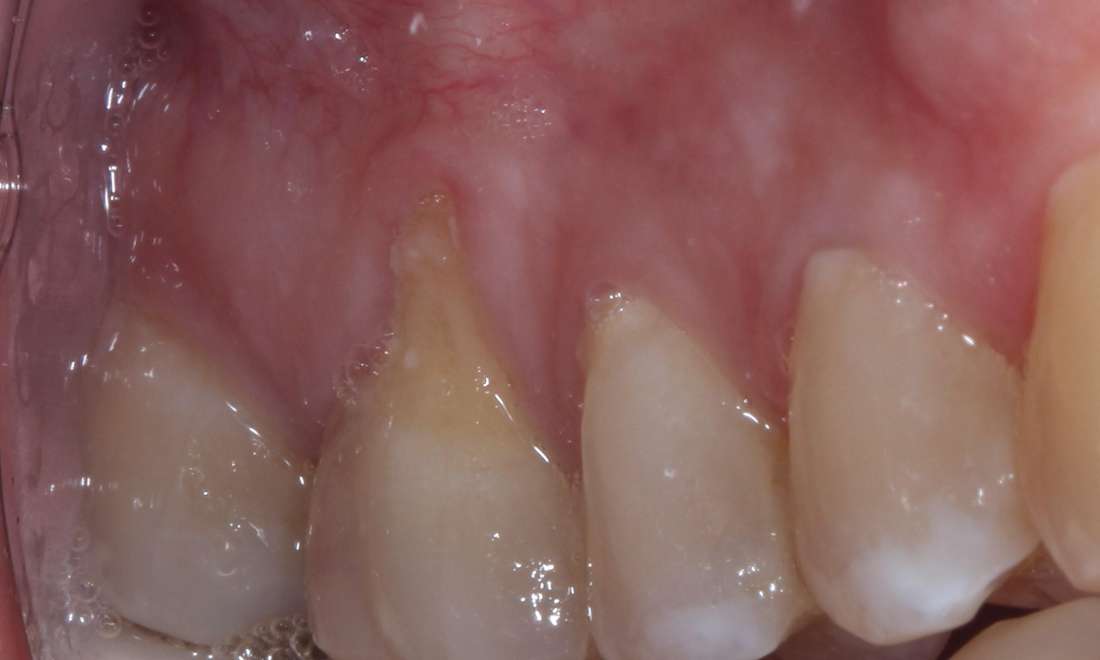

After: 3 months after gum grafting

After